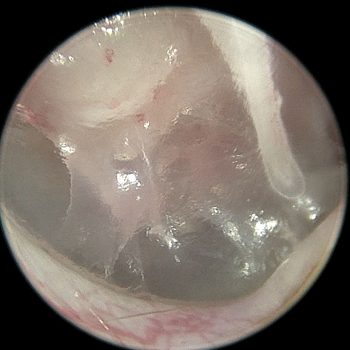

Diagnostyka endoskopowa zewnętrznych przewodów słuchowych (Otoendoskopia)

Głębokie płukanie przewodów słuchowych w znieczuleniu ogólnym

Myringotomia (nakłucie błony bębenkowej z oczyszczeniem z wydzieliny zapalnej) w celu diagnostyki i leczenia zapalenia ucha środkowego i wewnętrznego

Usuwanie ciał obcych (kłosy, bezoary)

Pobieranie biopsji tkanek zmienionych

Resekcję zmian nowotworowych w obrębie ucha zewnętrznego, także przy użyciu lasera